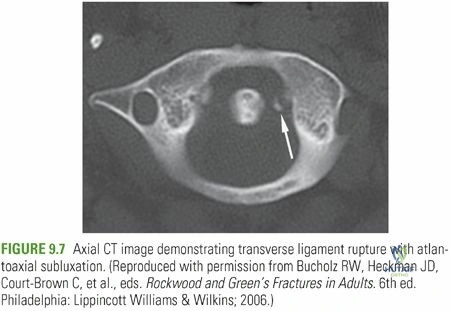

- الأشعة المقطعية (CT Scan): تُعد الأشعة المقطعية أكثر تفصيلاً من الأشعة السينية وتوفر صورًا مقطعية ثلاثية الأبعاد للعظام. تُستخدم للكشف عن الكسور المعقدة، وتقييم مدى الإزاحة، والتخطيط للجراحة بدقة بالغة. هي مفيدة بشكل خاص لتحديد كسور كلاب العظم الكلابي أو حديبة العظم المربعي التي قد يصعب رؤيتها في الأشعة السينية.